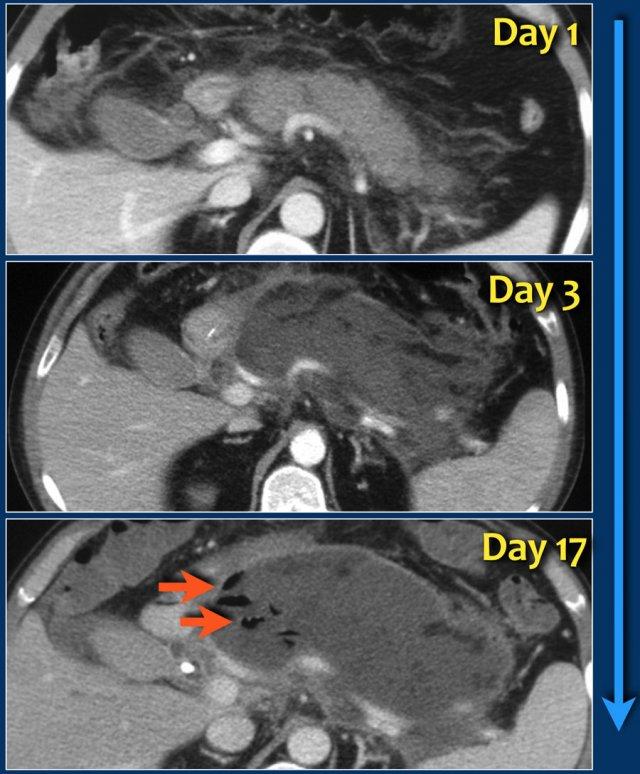

Các hình ảnh cho thấy tụy ngấm thuốc bình thường vào ngày thứ 1.

Khi tình trạng bệnh nhân xấu đi, CT lần hai được thực hiện vào ngày thứ 3.

Lưu ý phần lớn thân và đuôi tụy không còn ngấm thuốc, gợi ý viêm tụy hoại tử (các mũi tên).

CT lần đầu đã đánh giá thấp mức độ nặng của viêm tụy.

Bệnh nhân này tử vong vào ngày thứ 5 do hội chứng đáp ứng viêm hệ thống (SIRS) nặng và suy đa tạng.

Trường hợp này là ví dụ điển hình của hoại tử tụy nhiễm trùng.

- Vào ngày thứ 1, tụy ngấm thuốc bình thường và hình ảnh chỉ giống như viêm tụy thể phù nề kẽ nhẹ.

- Vào ngày thứ 3, tụy không ngấm thuốc, phù hợp với hoại tử.

Hoại tử cũng liên quan đến mô quanh tụy.

Đây là ANC – ổ hoại tử cấp tính. - Vào ngày thứ 17, có các bóng khí trong ổ hoại tử phù hợp với hoại tử tụy và quanh tụy nhiễm trùng.

Ổ hoại tử được bao quanh bởi một thành.